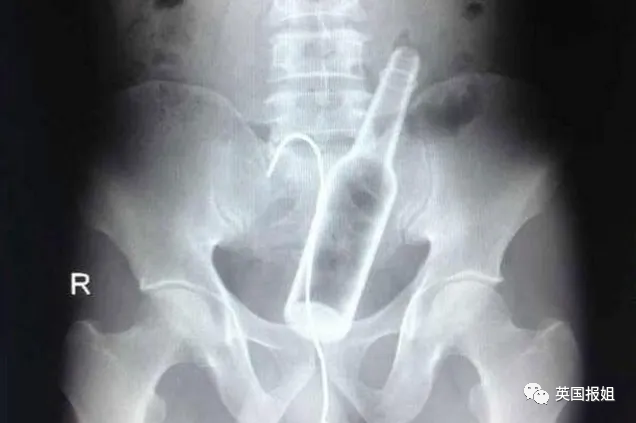

图中的患者是一名72岁的老翁,他自称在上厕所时不慎跌倒在了一个倒着的酒瓶上:

去年印度某医院急诊部闯入一名醉汉,该男子手拎着一根水管子,水管的另一头通向他的屁股。